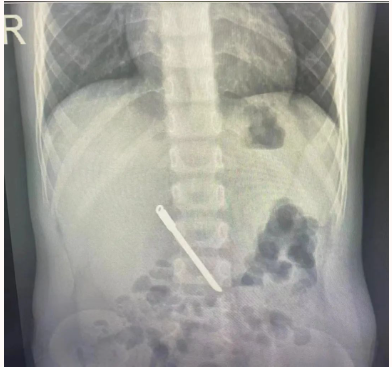

当地县医院完善腹部平片后告知家属无法取出,建议转院。

前天夜里,消化内科当值医师余波接诊这名误吞异物孩童。经详细了解患儿病情及阅片后,余波发现这娃胃口不小……

他与科室高年资医师合计后,认为该消化道异物较长,且为锋利异物,不能排外异物部分可能刺入消化道引起消化道穿孔,另外在取出过程中,由于患儿年龄小,麻醉风险大,取出过程中可能导致消化道损伤甚至穿孔的可能性,但时间拖的越长,消化道穿孔的可能性越大,孩子将更加危险!

在麻醉手术室医师的通力协助下,余波与科室团队凭借丰富经验、娴熟的技术操作,有条不紊的密切配合下,顺利地把患儿胃内这长度超过7cm尖锐异物顺利取出,整个过程10分钟以内,且胃内无损伤,患儿家属悬着的心终于放下了。留观一晚均无异常后,天明家属带着患儿离院。